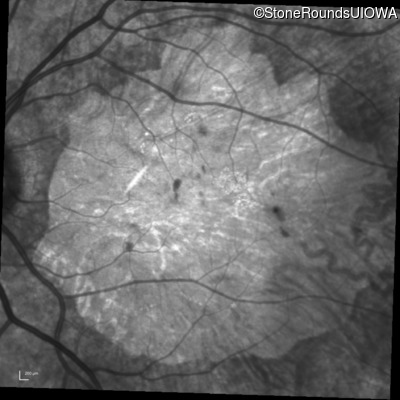

Infrared Fundus Photograph - Right - 10/200

Exemplar